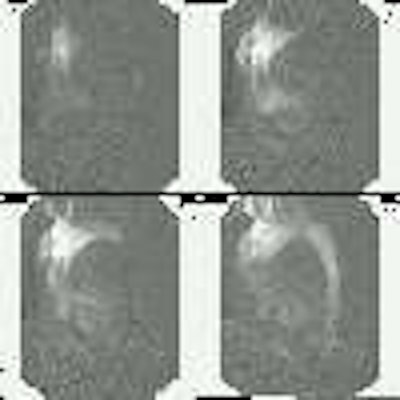

An angiogram demonstrated the point of rupture within the ascending aorta (arrow). A chest radiograph was obtained prior to the angiogram which demonstrated enlargement of the thoracic aorta (click here to view the CXR):